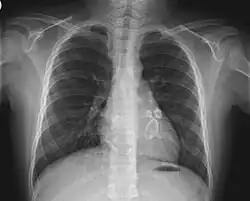

Die Diagnose eines kompletten Kawasaki-Syndroms wird klinisch gestellt und erfordert das Fieber und vier von fünf der anderen genannten Kriterien sowie den Ausschluss anderer Erkrankungen mit ähnlichen Symptomen. Dann kann die Diagnose auch schon nach fünf Tagen Fieber gestellt werden. Kinder, die diese Kriterien nicht erfüllen, werden als so genanntes inkomplettes Kawasaki-Syndrom diagnostiziert, wenn unten genannte Nebensymptome und/oder Laborbefunde teilweise oder überwiegend zutreffen. Dies tritt häufiger bei Kindern unter einem Jahr auf und ist hier wegen des erhöhten Risikos von Koronararterienaneurysmen (Nachweis durch transthorakale oder transösophageale Echokardiographie und gegebenenfalls Koronarangiographie[12]) besonders problematisch.

Virale und bakterielle Erkrankungen, Leptospiren, systemische Form der juvenilen idiopathischen Arthritis, Polyarteriitis nodosa, Quecksilbervergiftung. Bei inkomplettem Kawasaki-Syndrom bestehen zahlreiche weitere Verwechslungsmöglichkeiten. Bei Fieber unklarer Ursache sollte besonders beim kleinen Kind frühzeitig an die Differentialdiagnose Kawasaki-Syndrom gedacht werden und neben den Laboruntersuchungen auch eine Echokardiographie durchgeführt werden mit Untersuchung der Herzkranzgefäße.

Herzkranzgefäße

Der Langzeitverlauf der Erkrankung ist davon abhängig, ob Veränderungen an den Koronararterien auftreten. Bei etwa 25 % der unbehandelten Kinder entwickeln sich ein oder mehrere Aneurysmen. In diesem Fall wird die tägliche Einnahme eines leichten Blutgerinnungshemmers, etwa Acetylsalicylsäure (100 mg) bei Kindern empfohlen. Etwa die Hälfte dieser Aneurysmen bildet sich innerhalb eines Jahres wieder zurück. Bei etwa 20 % der Patienten kommt es im Laufe von Jahren zu Stenosen, die unbehandelt wiederum in fast der Hälfte der Fälle zum Herzinfarkt führen.